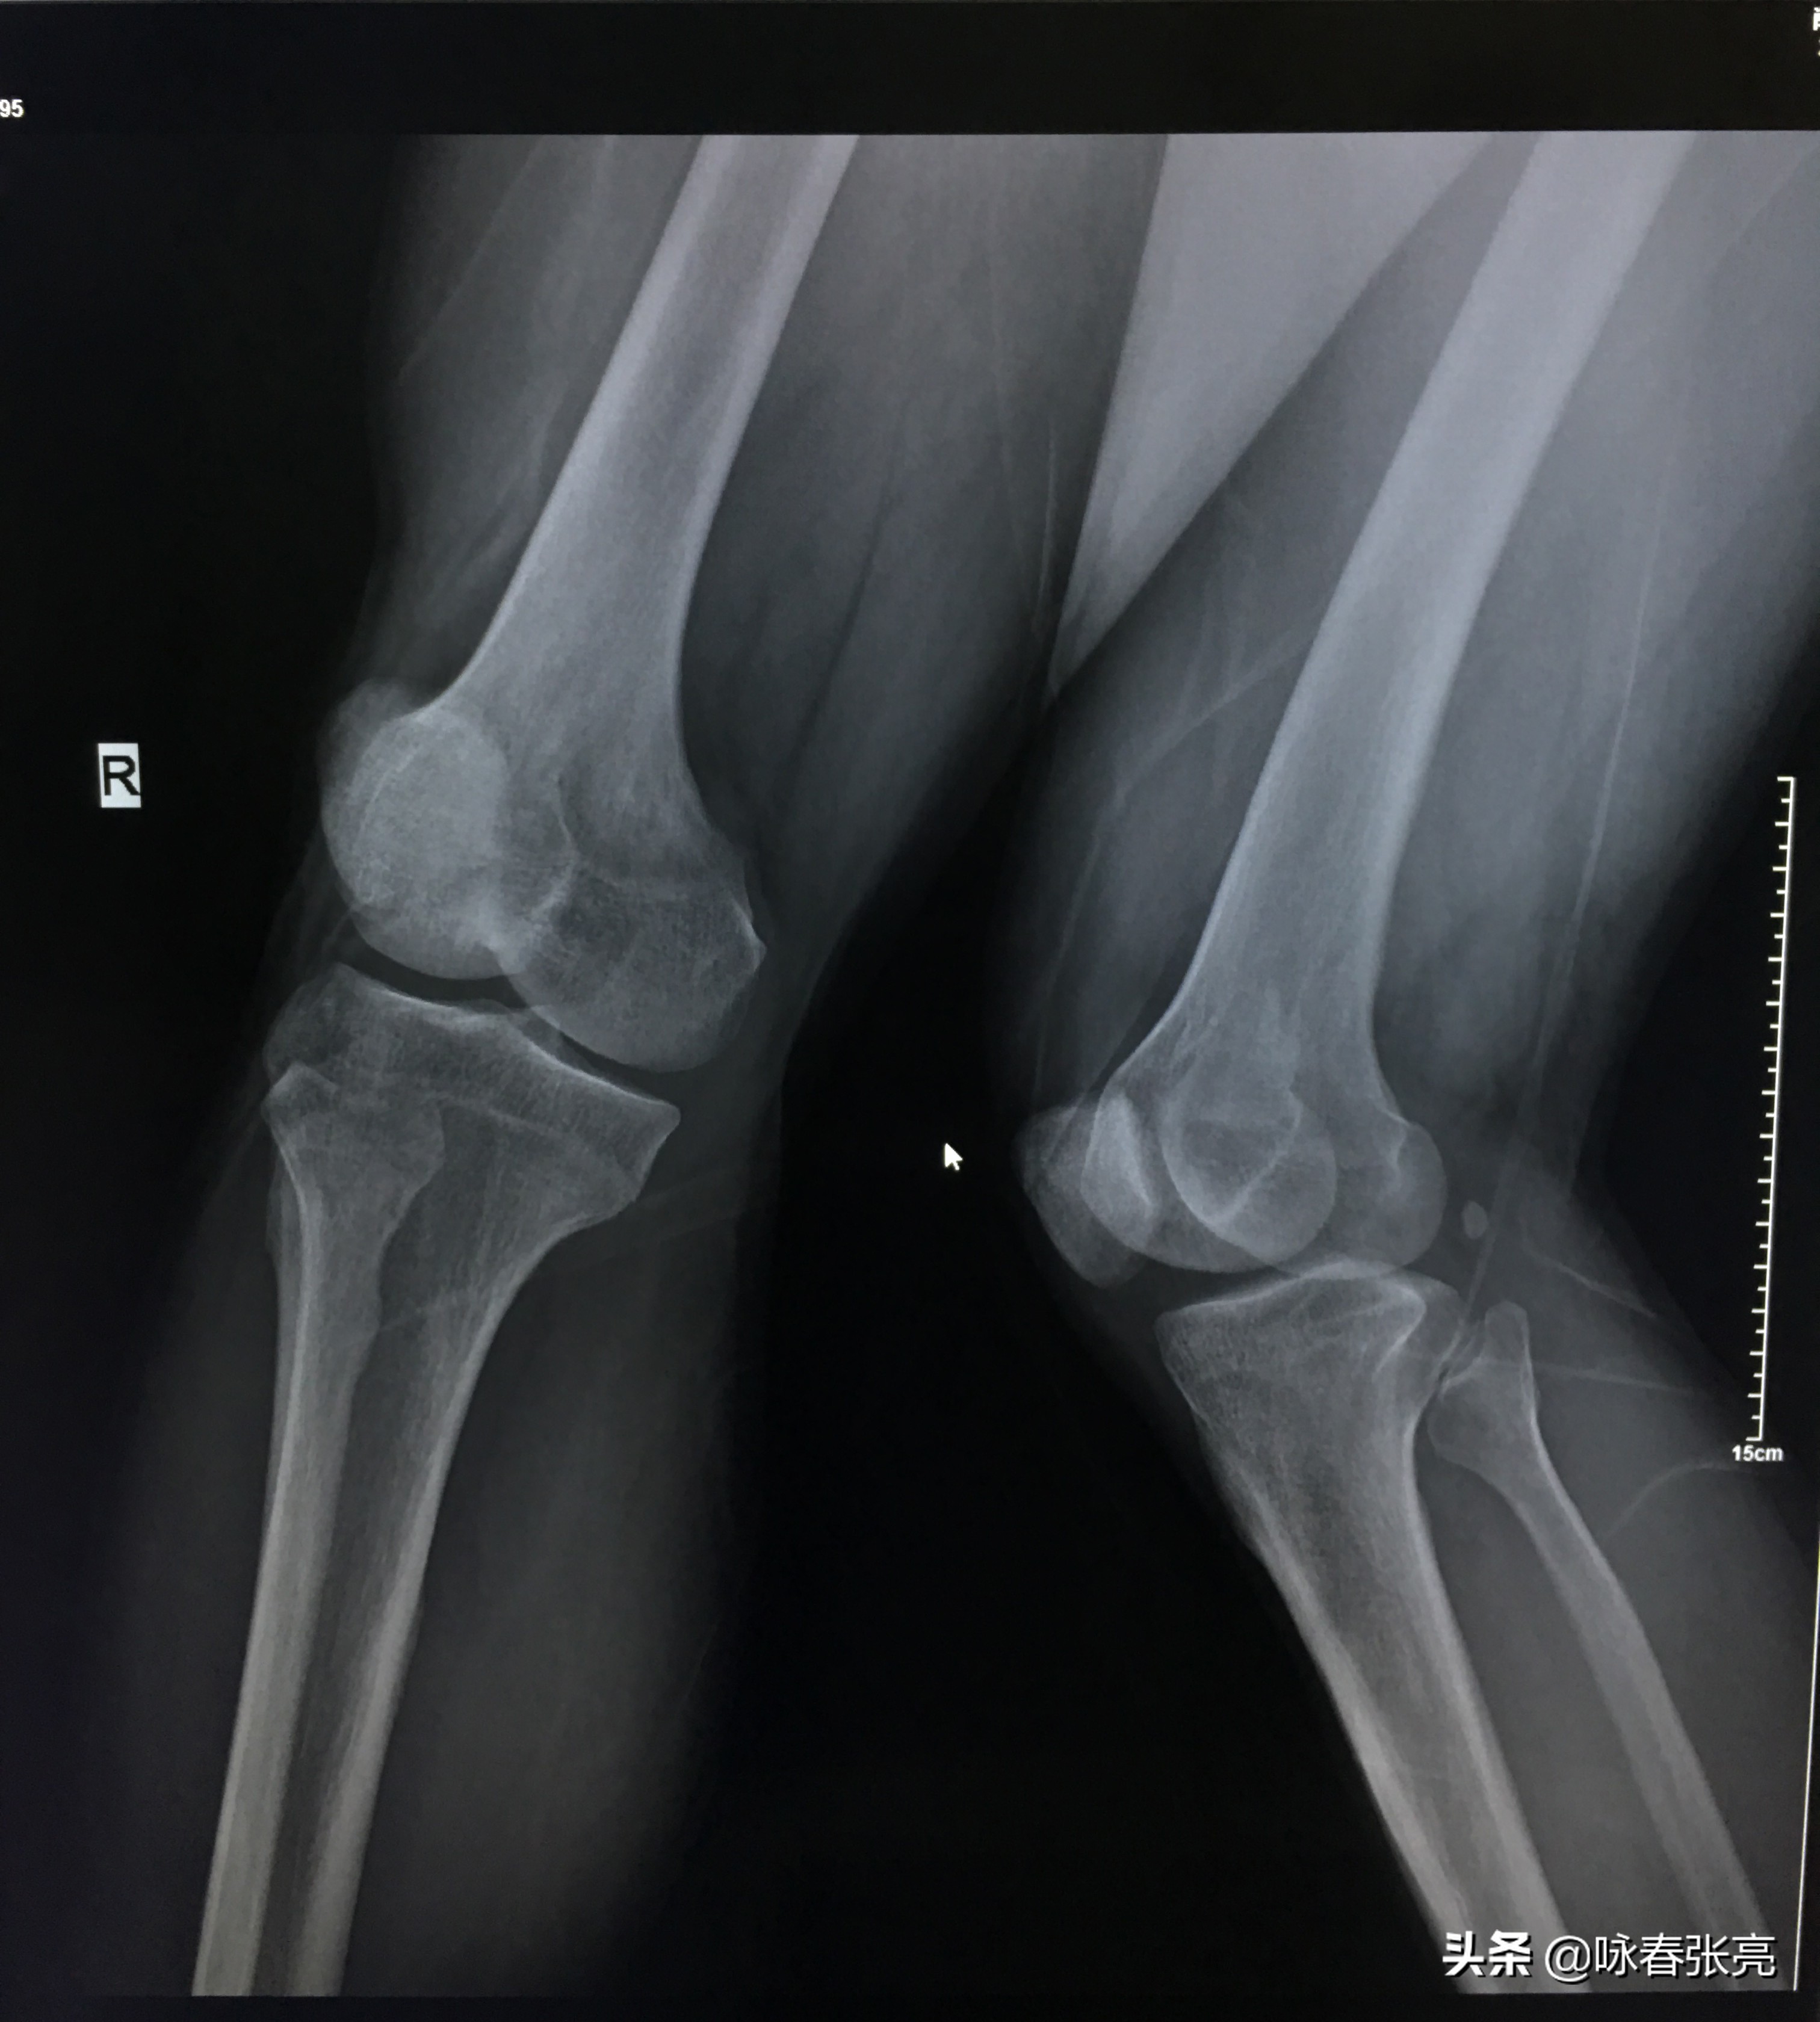

咏春拳钳羊马 DR

咏春拳二字钳羊马 DR